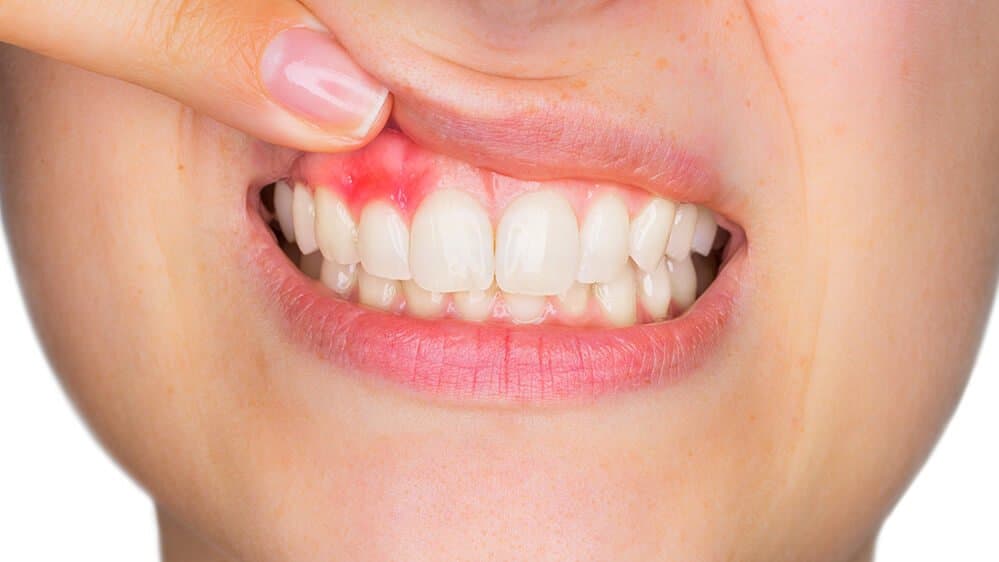

Gum Inflammation

Poor oral hygiene or conditions like gingivitis can cause swollen gums, making them more visible.